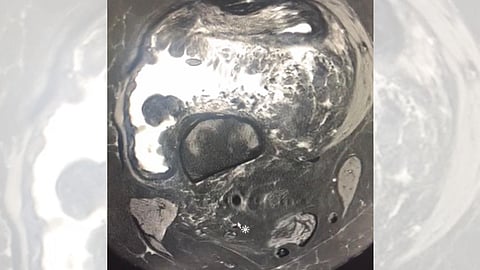

وأوضحت أن فريقًا طبيًّا في مستشفى المدينة المنورة، تمكَّن من إجراء عملية استئصال ورم في الركبة اليمنى لمريضة في الستين من عمرها بعد معاناة استمرَّت عدة أعوام، وقد تكللت العملية بالنجاح.